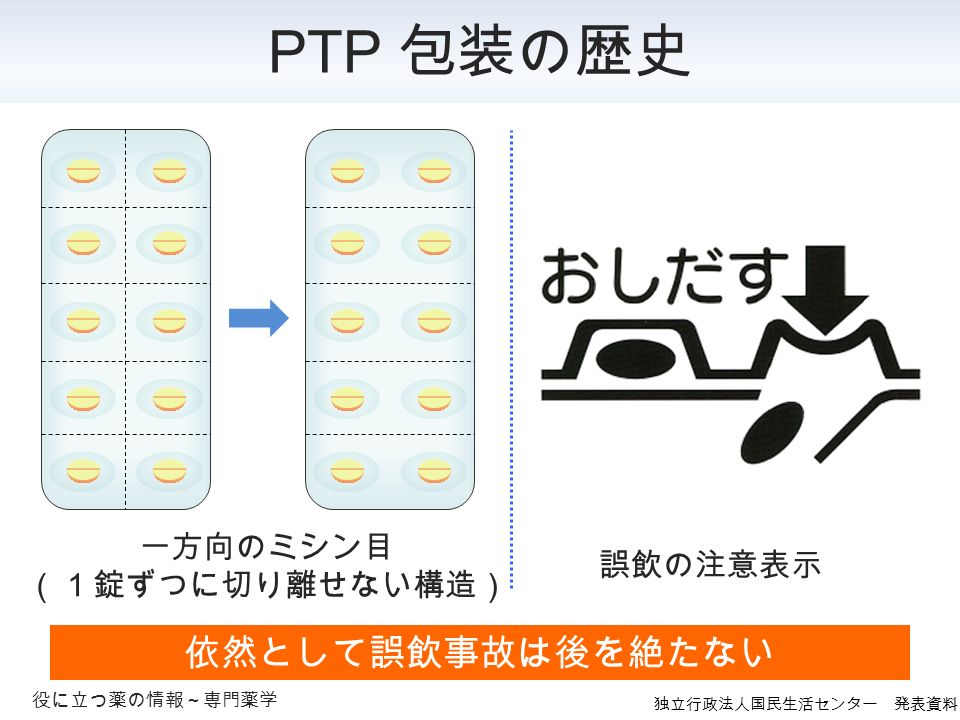

Https Www Nichiyaku Or Jp Assets Uploads Pharmacy Info Ptp Pdf

Https Www Nichiyaku Or Jp Assets Uploads Pharmacy Info Ptp Pdf

薬のptpシートを1錠ずつバラバラにするのは止めて下さい 第4報

ptp包装シートの誤飲 平成23年4月 日本薬剤師会 Ppt Download

ptp包装シートの誤飲 平成23年4月 日本薬剤師会 Ppt Download

Https Www Nichiyaku Or Jp Assets Uploads Pharmacy Info Ptp Pdf

ptp包装シートの誤飲 平成23年4月 日本薬剤師会 Ppt Download

Ppt ptp包装シートの誤飲 Powerpoint Presentation Free